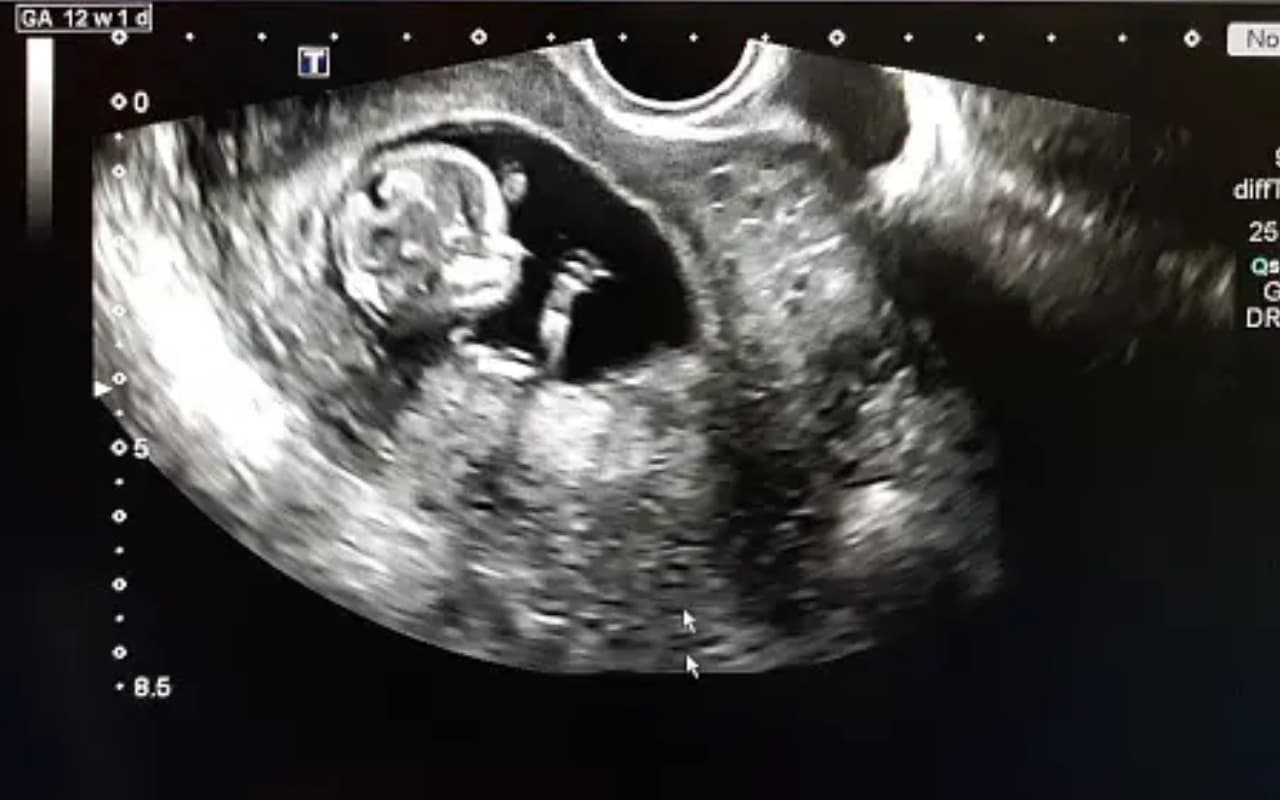

Pregnancy Care Tips: गर्भावस्था किसी भी महिला के लिए काफी महत्वपूर्ण वक्त होता है जहां उसके और गर्भ में पल रहे बच्चे की देखभाल के लिए सतर्कता की आवश्यकता होती है. कई महिलाएं इस दौरान घंटों मोबाइल में लगी रहती हैं और चिप्स, चॉकलेट से लेकर तमाम जंक फूड खाती रहती हैं. इस आदत को बदलना बहुत जरूरी है.

बहुत अधिक आरामतलबी की आदत के कारण गर्भवती महिलाओं का बढ़ता शुगर का लेवल गर्भ में पल रहे शिशुओं की सांसें तक छीन रहा है. साथ ही दिमाग और शरीर का विकास भी रोक रहा है.

स्टडी में पाया गया कि हाइलेवल शुगर का नवजात पर कई दुष्प्रभाव पड़ता है. इससे बच्चे की रीढ़ की हड्डी और दिमाग का समुचित विकास नहीं होता.

शिशुओं में किडनी संबंधी जन्मजात दिक्कत के साथ मोटापा से पीड़ित होने और शरीर के विकास में यह समस्या बाधा डाल सकती है.

हाइ शुगर के कारण गर्भ में होने वाली अधिकांश मौतें सातवें या आठवें महीने में होती है. इससे बचने के लिए गर्भावस्था के दौरान जांच और इलाज कर बीमारी को कंट्रोल किया जा सकता है.